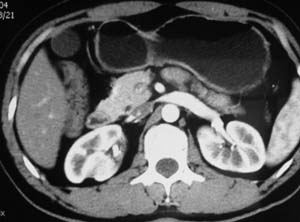

以下是引用子期在2010-3-19 20:47:00的发言:[br]血管畸形的ct增强应该有明显强化,本例并不相符合。本例双肾局部的略低密度影,累及肾盂,局部皮质明显变薄、内陷,增强扫描有轻度的强化,应考虑为炎性病变,患者为年轻男性,累及双肾的感染以结核较常见,可以没有明显的临床症状,尿中有时候也并不能查出什么;肾脓肿常有明显感染中毒症状,本例不符,另外一般的肾盂肾炎或肾小球肾炎通过小便就可确诊,其它还不能排除的是黄色肉芽肿性肾盂肾炎,然而单凭ct一般也很难鉴别。